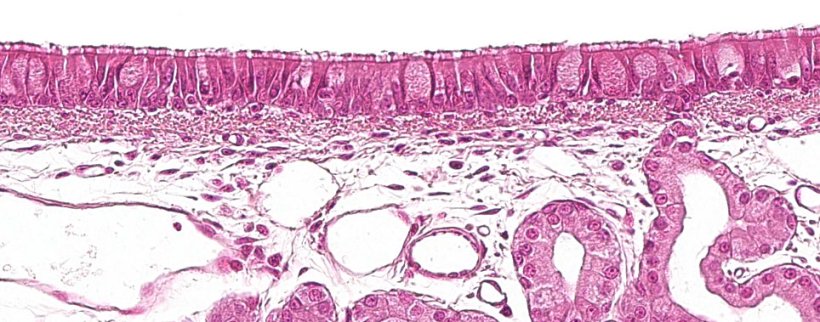

图1:具有杯状细胞的纤毛假复层上皮,是呼吸系统的特征.